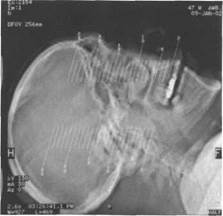

При ряде диагностических ситуаций дополнительно используется акси­альная проекция по стандартной методике (рис. 2, б). Показанием для иссле­дования в аксиальной проекции считается:

Рис.2 б. Направление сканирова­ния для получения изображения в аксиальной проекции.